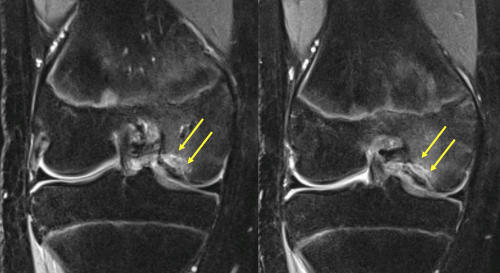

Osteokondritis dissekans tanısı için ortopedi doktorunuzun yapacağı ayrıntılı bir diz muayenesi sonrası röntgen grafileri hastaların çoğunda yeterlidir (Resim 1). Bilgisayarlı tomografi (BT) ve Manyetik Rezonans Görüntüleme (MRG) gibi ileri görüntüleme yöntemleri hastalığın evresinin belirlenmesi, tedavi planının yapılması ve tedavi sonucunun değerlendirilmesi için gereklidir (Resim 2). Artroskopik değerlendirme, evreleme ve tedavi planı için en önemli araçtır. Bir kamera kullanılarak eklem içi incelenir, parçanın boyutları, yerleşimi, altındaki yatağa olan bağlantısı ve vida tespitine uygun olup olmadığı nihai olarak artroskopi sırasında değerlendirilir ve tedavi aşamasına geçilir.

Ergenlik öncesinde saptanan ve altındaki canlı kemik yatağından ayrılmamış olan osteokondritis dissekans, çocukların yarısından fazlasında ameliyatsız iyileşebilir. Bunun için sportif aktivite kısıtlanır ve 6 aylık aralarla MRG takibi yapılır. Üzerindeki kıkırdağın bütünlüğü bozulmamış ve MR’larda ayrılma bulgusu yoksa, ölü kemik vücut tarafından onarılarak 2 yıl içinde iyileşme sağlanabilir (Resim 3). Bu takip için kaliteli bir MR görüntülemesi şarttır. MRG’lerde ayrılma bulgusu saptanan çocuklarda cerrahi tedavi gerekli olur. Her iki dizde osteokondritis varsa, seyirleri aynı olmayabilir. Bir taraf iyileşirken diğer taraf ayrılıp ameliyat gerektirebilir.